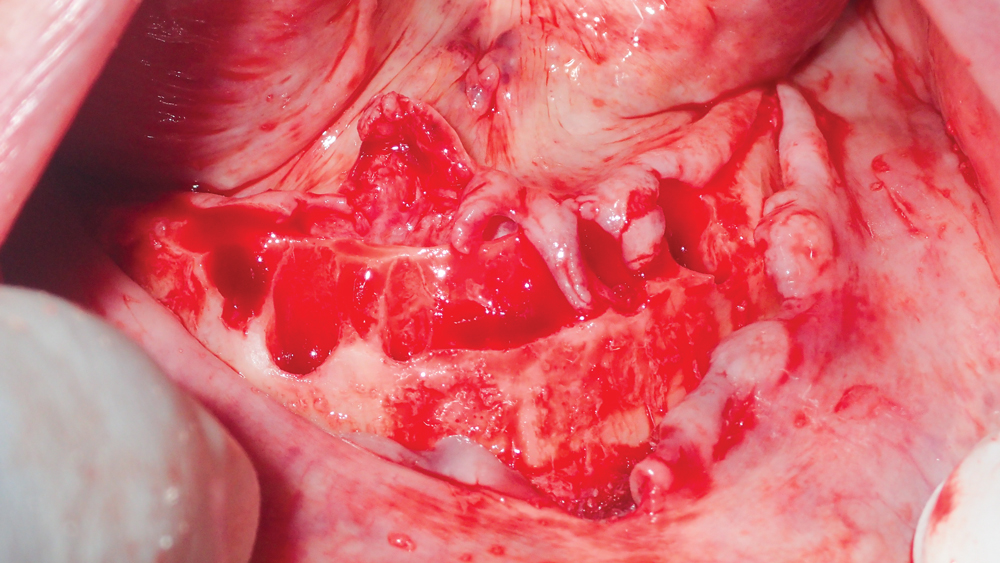

This patient was unhappy with the esthetics of her existing upper denture as well as the discomfort and instability caused by her loose-fitting mandibular partial denture. Although her concerns with the maxillary denture could be addressed with a new, more esthetic appliance, she preferred implant treatment for her mandible, where a fixed solution was needed to adequately restore function, stability and comfort.

The patient’s remaining mandibular teeth were extracted followed by immediate implant placement and delivery of a fixed provisional appliance. After integration of the implants, the prosthetic designs for the new upper denture and lower implant restoration were determined in tandem. Ultimately, the dual-arch restorations addressed the functional and esthetic challenges of the case while staying within the financial means of the patient, demonstrating the benefits of a flexible, multifaceted approach to restorative dentistry.